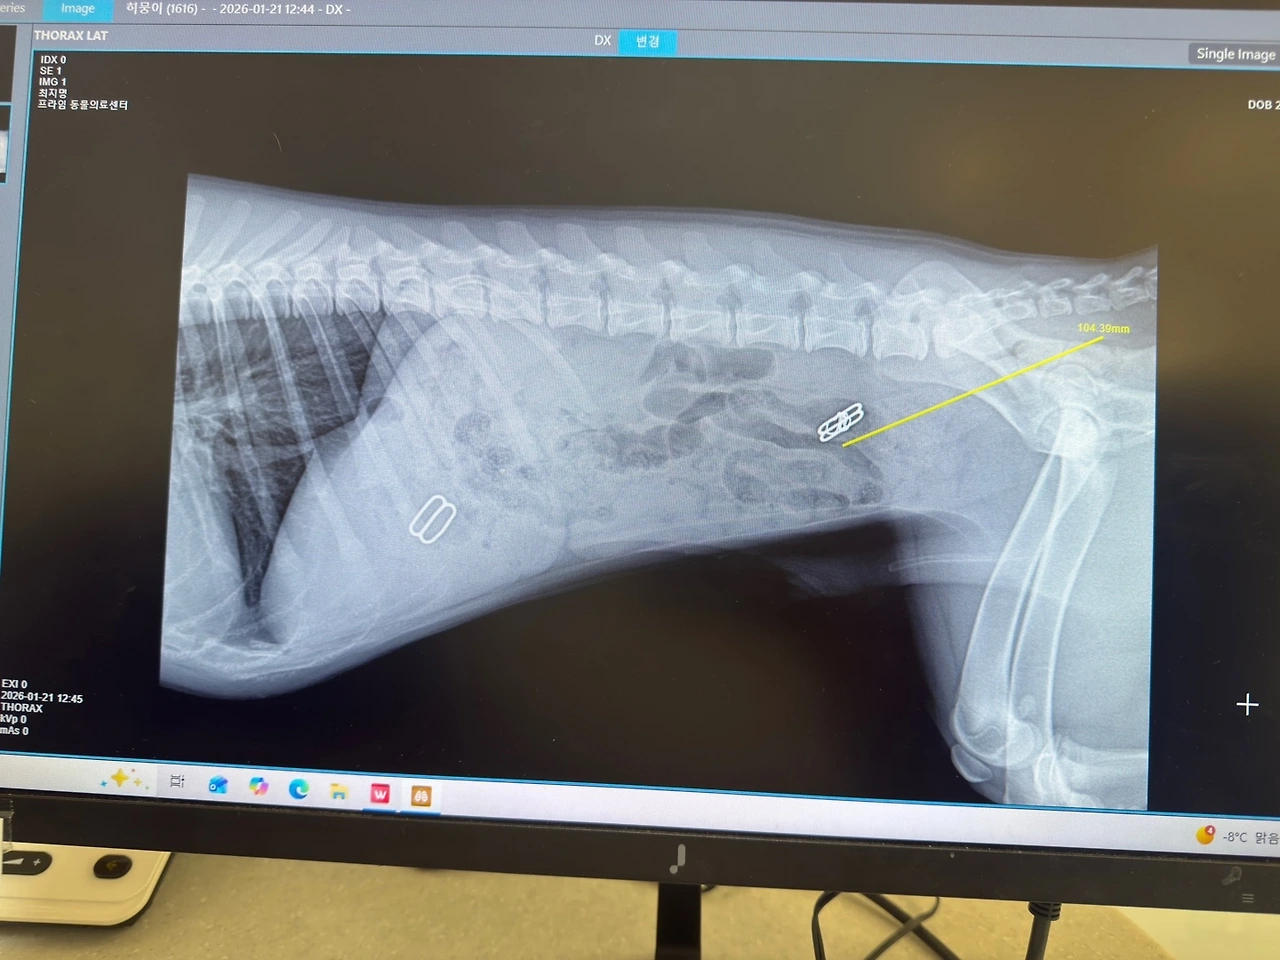

참고로 지난 두 달 동안, 생사를 오고 가는 일도 몇 번 있었다. 갖고 놀던 장난감을 삼켜서 위 내시경과 개복 수술의 위기도 있었고(일주일 만에 똥으로 나옴), 초코 단백질 파우더를 먹어 위세척의 위기도 있었다. 다행히도 우리 마음만 졸이게 하고 아직까진 건강하다. 똥개자식.

히뭉이 뱃속에 있던 나의 속옷 끈...